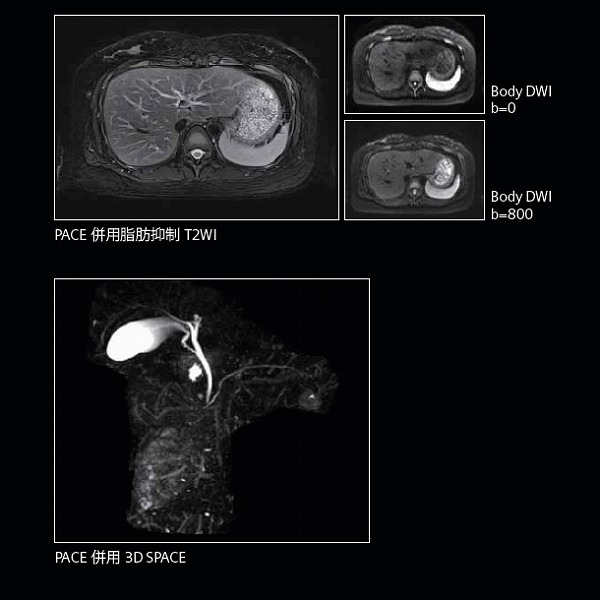

●高密度コイルTim4Gと最新ソフトウェアバージョンE11によるさまざまな臨床へのアプローチで、高精細画像や臨床有用性の高い画像の描出を可能にします。

●体幹部や末梢血管、脳灌流画像を造影剤を用いることなく描出することで被検者の負担の少ない検査を目指しています。